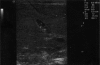

Fig. 1

Multiple hyperechoic structures with posterior reverberation in 4 days old neonate.